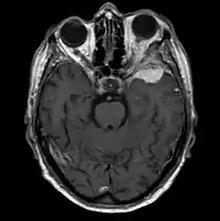

Sphenoid wing meningiomas are diagnosed by the combination of suggestive symptoms from the history and physical and neuroimaging by magnetic resonance imaging (MRI) or computer averaged tomography (CT). Tumors growing in the inner wing (clinoidal) most often cause direct damage to the optic nerve leading especially to a decrease in visual acuity, progressive loss of color vision, defects in the field of vision (especially cecocentral), and an afferent pupillary defect. If the tumor continues to grow and push on the optic nerve, all vision will be lost in that eye as the nerve atrophies. Proptosis, or anterior displacement of the eye, and palpebral swelling may also occur when the tumor impinges on the cavernous sinus by blocking venous return and leading to congestion. Damage to cranial nerves in the cavernous sinus leads to diplopia. Cranial nerve VI is often the first affected, leading to diplopia with lateral gaze. If cranial nerve V-1 is damaged, the patient will have pain and altered sensation over the front and top of the head. Horner's syndrome may occur if nearby sympathetic fibers are involved.

Tumors found in the external third of the sphenoid are of two types: en-plaque and globoid meningiomas. En plaque meningiomas characteristically lead to slowly increasing proptosis with the eye angled downward. Much of this is due to reactive orbital hyperostosis. With invasion of the tumor into the orbit, diplopia is common. Patients with globoid meningiomas often present only with signs of increased intracranial pressure. This leads to various other symptoms including headache and a swollen optic disc. The differential diagnosis for sphenoid wing meningioma includes other types of tumors such as optic nerve sheath meningioma, cranial osteosarcoma, metastases, and also sarcoidosis. Following the physical exam, the diagnosis is confirmed with neuro-imaging. Either a head CT or MRI with contrast such as gadolinium is useful, as meningiomas often show homogenous enhancement. Angiography looking for signs like stretched arteries may be used to supplement evaluation of vascular involvement and to determine whether embolization would be helpful if surgery is being considered.